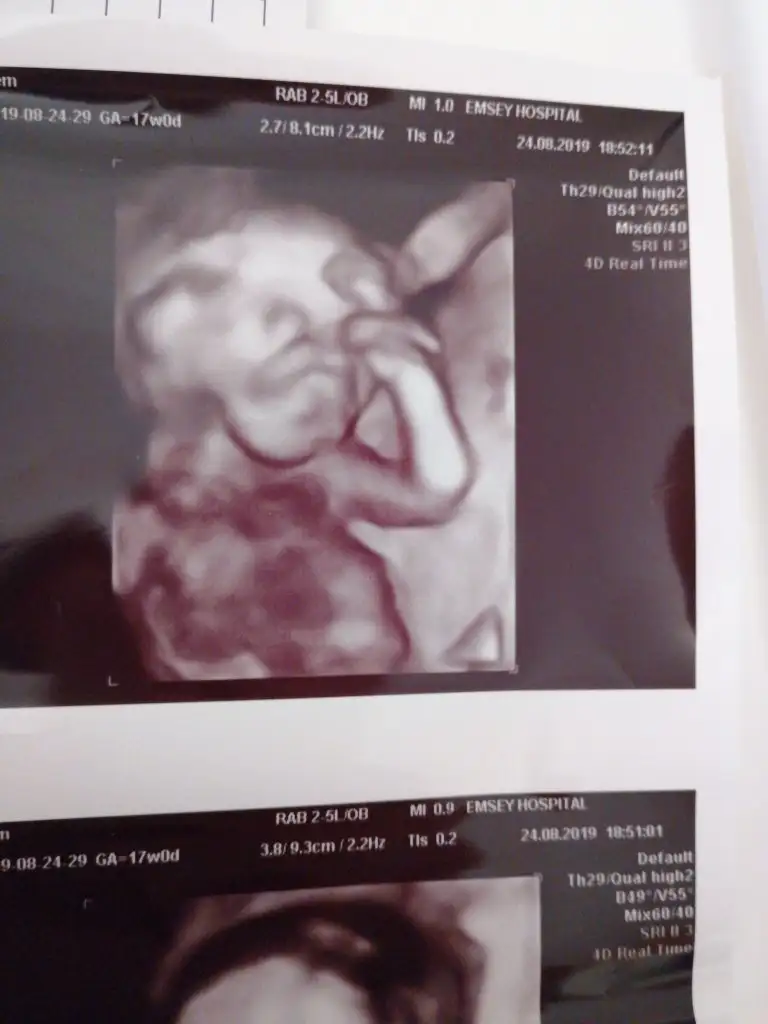

18cm, 220 gram olmuş sağlıkla gelsin kuzumuz 😍😍 detaylıyı da kendi hastanemizde 500 liraya olucak mış,

bu da resmimiz tontikimiz 😍